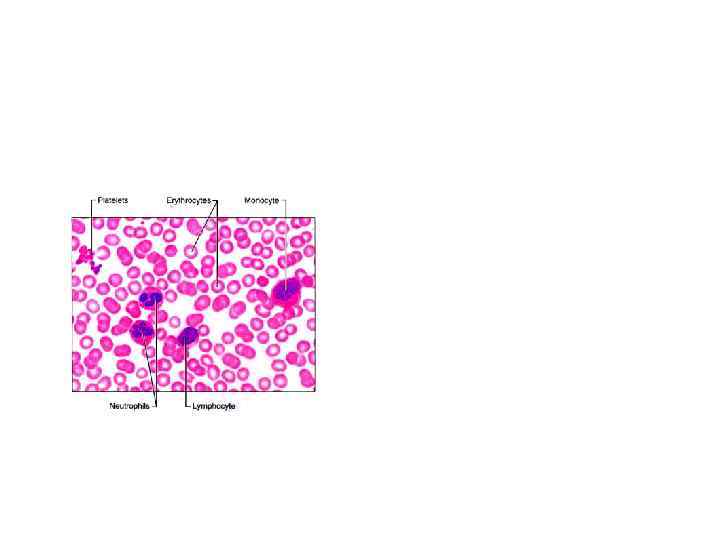

• Клинико-диагностическое значение лабораторных показателей в гематологии • РАМН ГНЦ, академик А. И. Воробьев, 2001 • • МАЗОК КРОВИ Нормальная лейкоцитограмма взрослых: Нейтрофилы палочкоядерные 1 -5% Нейтрофилы сегментоядерные 40 -50 % Лимфоциты 20 -45% Моноциты 3 -8% Эозинофилы 1 -5% Базофилы 0 -1%

• Клинико-диагностическое значение лабораторных показателей в гематологии • РАМН ГНЦ, академик А. И. Воробьев, 2001 • • МАЗОК КРОВИ Нормальная лейкоцитограмма взрослых: Нейтрофилы палочкоядерные 1 -5% Нейтрофилы сегментоядерные 40 -50 % Лимфоциты 20 -45% Моноциты 3 -8% Эозинофилы 1 -5% Базофилы 0 -1%

• В окрашенных мазках крови подсчитывают лейкоцитарную формулу + процентное соотношение разных видов лейкоцитов. Исследование лейкоцитограммы состоит в дифференциации в мазке 200 -500 расположенных подряд лейкоцитов.

• В окрашенных мазках крови подсчитывают лейкоцитарную формулу + процентное соотношение разных видов лейкоцитов. Исследование лейкоцитограммы состоит в дифференциации в мазке 200 -500 расположенных подряд лейкоцитов.